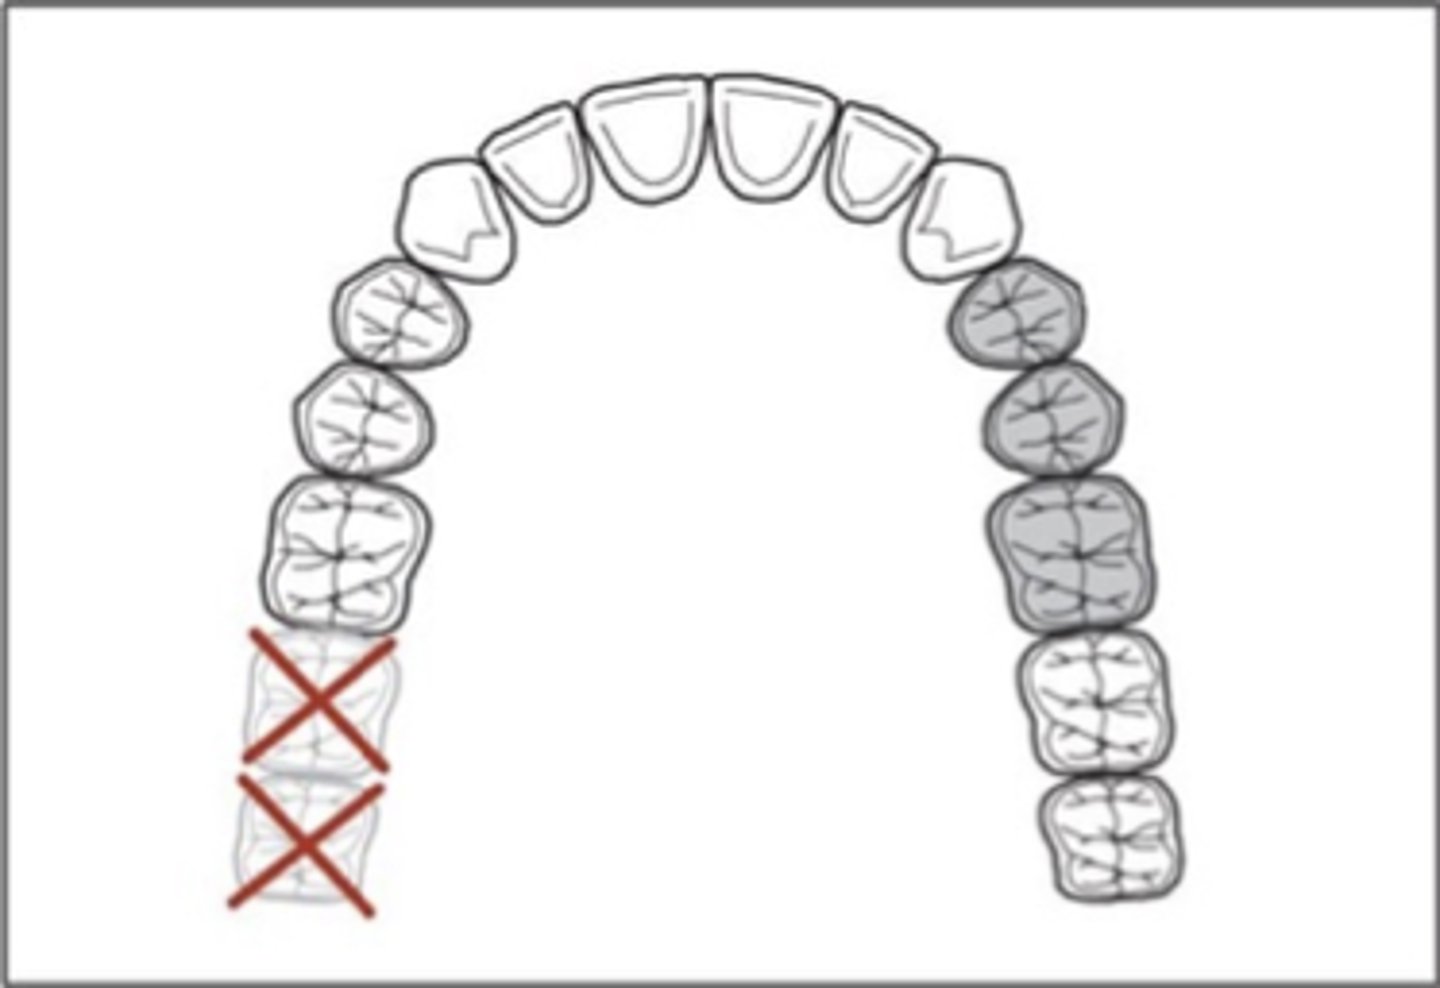

unilateral edentulous area located posterior to the natural teeth

Kennedy Class III

Class II Mod 2

which Kennedy Class?